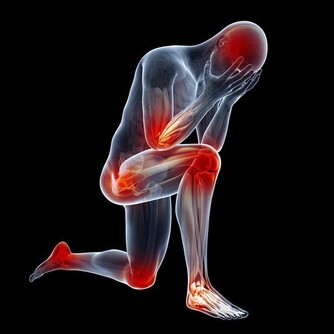

腳因為與心臟距離最遠,因此,血從心臟流到腳尖的過程也較長,很容易出現末梢迴圈障礙,導至供血不足;一些新陳代謝的廢物和各種毒素可能在足部積存下來,產生某種毒素,引起關節炎和一些器官的病變。 古人經常泡腳,用手按摩自己的腳心,天天散步,就是把氣血引到腳上去,只要新鮮的血液能引到腳上,令到氣血暢通,便可帶走在足部積存的代謝後廢物,運到腎臟處理後排出體外。 下肢血液回流心臟時,除胸腔吸氣運動產生的胸腔負壓和心臟舒張期產生的負壓吸引等作用外,主要依靠下肢肌肉在運動時的肌肉擠壓作用,特別是小腿肌肉(腓腸肌和比目魚肌是主要的「肌肉泵」)的擠壓作用,並藉助於靜脈瓣膜的單向開放功能,使靜脈血由遠端向近端、由淺靜脈向深靜脈流動,最後回流到心臟;我們把小腿肌肉的擠壓作用稱作「肌肉泵」作用,亦被稱為「第二心臟」。 下肢血液迴圈功能不佳,可影響人體各個器管的生理功能,導致各種疾病的發生,由此可以看出離心臟最遠的腳部肌肉的重要性。 雙腳的血液迴圈順暢,將促使全身的血液大循環亦處於良好狀態,你就可以延緩衰老。

下蹲運動能夠治病強身的原理 人蹲下去,身體變成三折疊,被擠壓的血管收縮,氣血沖向全身未被擠壓的血管,迫使它們擴張、鼓起來;人一站起來,全身氣血又沖向原來被擠壓的血管,為它們灌滿血液;在這樣的一蹲一起、一壓一放、一沖一回的氣血往復運動中,就像涮瓶子一樣,使全身血管得到了反復沖洗,使血管軟化、加快血液迴圈和體內的新陳代謝、啟動免疫系統,增加了高密度膽固醇、靈敏了壓力感受器、把一些有害、有毒的代謝產物可迅速得以清除,人體自然就健康了。 下蹲可以激發經絡功能 雙腳是運行氣血、聯絡臟腑、溝通內外、貫穿上下的十二經絡的重要起止部位;加上奇經八脈,下蹲運動可以自然地激發這近20條經脈的經氣。 下蹲運動的其他作用和好處: ◇與長壽有關 對一些百歲健康老人的生活方式調查發現,他們從事田地耕作,蹲在池塘邊淘米、洗菜、洗衣服、廁所也是蹲的…這就強健了他們的腰腿,達到了祛病除疾的作用。 ◇強健關節和骨骼 下蹲可增強腰、髖、膝和踝關節的活動範圍,增強膝關節的靈活性,延緩關節的老化,關節如果活動少,會使骨骼變得脆弱,鈣就會流失到血液中,而且會積存在腎臟和膀胱中,造成排尿困難以及細菌繁殖等不良後果,所以經常使用和活動關節是永保年輕的關鍵。 ◇可以增強肌肉力量 常做下蹲運動可以增強肌肉力量,尤其是下肢的肌肉力量;兩條腿的力量增強了,可有效預防跌倒,走路時您會感到身體輕鬆,且生命充滿活力。 人體肌肉如果適度使用,將會更發達,但廢棄不用或過度使用就會退化。 ◇可改善血管功能 可以擴張微、小動脈血管,減少心臟外周阻力,可以改善微、小動脈血管壁的彈性,有效地降低血壓。 ◇可以降低血脂 下蹲運動通過刺激經絡系統,可使脾經運化功能增強,促進血管壁粥樣斑塊的分解,降低血液的粘稠度,減少血液中甘油三酯和低密度脂蛋白,增加高密度脂蛋白,促進脂代謝,進而改善血管的彈性,有效防治動脈粥樣硬化,對預防心、腦血管意外的發生有重要意義。 ◇可以促進新陳代謝 下蹲運動主要靠兩條腿的屈伸來支撐軀幹以上身體的重量;當下蹲時,身體的重量向下壓擠腿部肌肉中的血管,加快下肢的靜脈血液流向心臟;當身體起來時,解除了身體重量對下肢肌肉的擠壓,從心臟泵出來的動脈血快速進入下肢,如此反復下蹲、起來、再下蹲,有如「唧筒」的作用,加快血液迴圈和新陳代謝;血液迴圈加強了,回心血量增加,有效地改善心肌的血液供應和新陳代謝;血液迴圈加強了,胰腺等臟腑器官的營養與氧氣供應得到充分改善,胰島素分泌細胞的功能恢復正常,可有效地控制糖尿病。 ◇增強性功能對 下蹲運動可以強健大腿內側的肌肉,包括直接與性能力相關的長收肌,另外由於能使容易淤積在此的血液和淋巴液回流,也就促進了生殖器官的活躍,人到中年後性功能會逐漸減退,如果能長期堅持下蹲,性功能會逐漸提高。 ◇減肥效果明顯 下蹲能消耗很多熱量,可以減掉身上多餘的脂肪,特別臀部和大腿堆積的脂肪;另外下蹲時由於擠壓腹部,想知道自己一生愛情財運如何,添加大師微信:byou66 ,免費給你算命!促進腹腔臟器周圍的脂肪燃燒分解,減少脂肪的積累,亦可刺激胃腸的食物消化,促進消化酶的分泌。 ◇鍛煉可以使精神放鬆 可以暫且拋開煩惱、放下生活的壓力、使人的精神得到放鬆,調節情緒,增加生活樂趣,這對人的身心健康都有好處。 ◇能延緩大腦的衰退 如果腿衰老了(主要原因是肌肉、骨骼、關節的老化),大腦也會隨之衰老;腿衰老後人的活動減少,感官接受新資訊的機會減少,來自外界的刺激少了,大腦細胞也就不再活躍,人就會變得癡呆起來;下蹲可以加強腿的活動能力,增強和外界接觸,不但能夠延緩大腦的衰退,而且可以進一步增智開慧。 動作要領 下蹲的姿勢:正確的姿勢應該是從動作開始到結束,頭部到腰部的軀幹要始終保持筆直伸展的狀態,臀部要向身後撅起。 開始姿勢:要全身放鬆,兩腿分開,略比肩寬(或與肩同寬),自然地站立;腳尖的方向基本是倒八字形,以腳的第二趾的方向為准;下蹲時,膝蓋的方向要在第二趾的延長線上,這樣做起來比較自然而不吃力。 結尾姿勢:膝蓋彎曲,直到大腿與地而平行為止(視乎各人體力,老年人或初練者可先取用半蹲或1/4蹲);在完全蹲下時停頓片段最能鍛煉肌肉。 向上站起時的姿勢:向上站起時的要點是感覺整個腳掌在向下推壓地面,直立站起。 下蹲時的速度:1次下蹲的速度(時間)大致標準是5秒鐘1次(視乎體力,以舒適為佳),到了蹲的姿勢時,有意放慢速度更好。 呼吸方法:一邊下蹲,一邊吸氣;一邊站起來,一邊呼氣。 鍛煉的次數:注意量力而行,循序漸進,以1天做30次以上為宜;體弱的人開始少做,有體力的人可多做。 做下蹲運動的頻率:如果想維持健康或消耗脂肪的話,是應該每天鍛煉的。